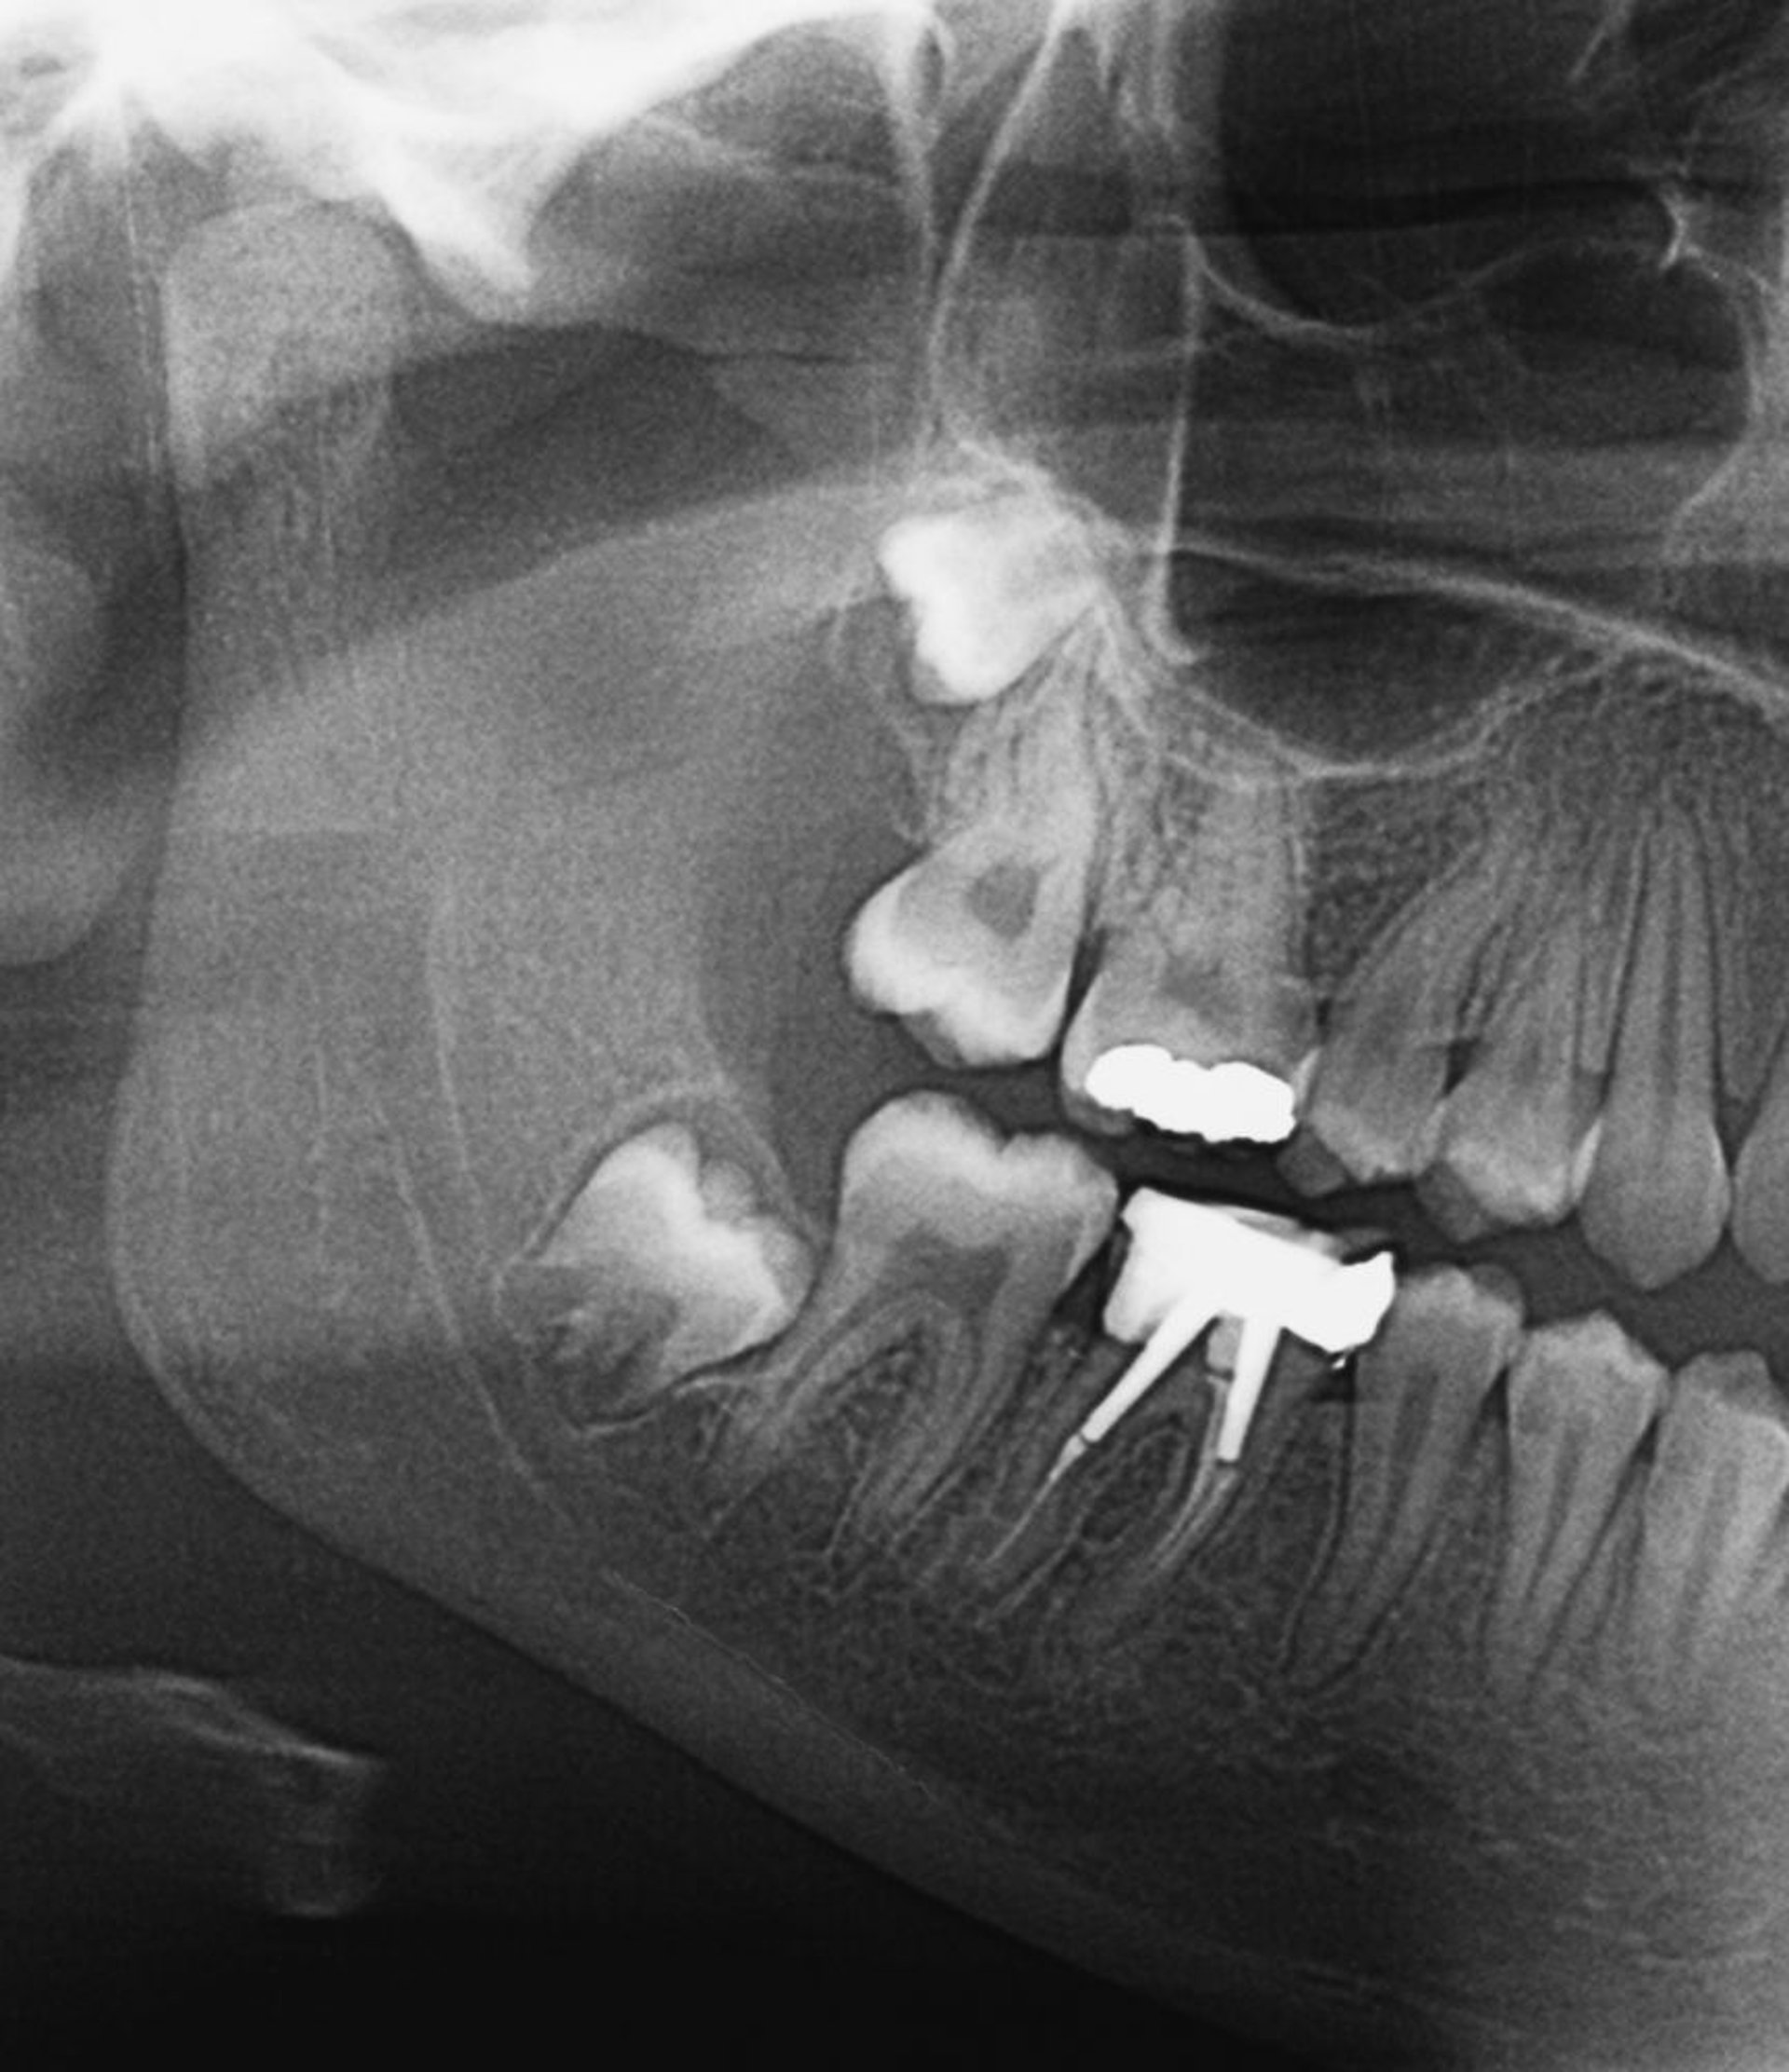

Dentes do siso impactados

Essa radiografia mostra os dentes do siso impactados. À medida que os dentes do siso se irrompem, ou se são parcialmente impactados, a pericoronite pode se desenvolver.

ZEPHYR/SCIENCE PHOTO LIBRARY